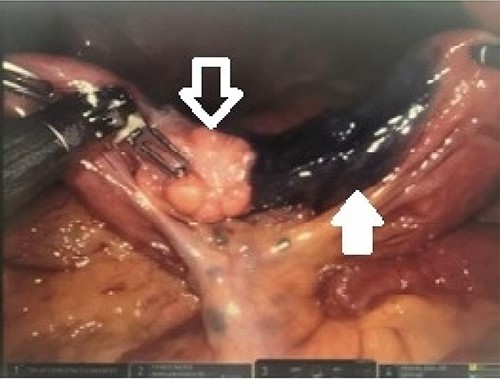

Endoscopic ultrasound (EUS) revealed a 1-cm submucosal antral mass. Due to size and wall involvement, pancreatic rest was suspected, though the jejunal lesion multifocal carcinoid tumor remained in the differential. An endoscopic mucosal resection of gastric lesion was performed, but pathology again was inconclusive. As the jejunal mass was noted to be 20–30 cm distal to the ligament of Treitz, and a miniprobe EUS was utilized to access this location. The small bowel lesion was hypoechoic, well demarcated, 2 cm and arose from the muscularis propria. Due to the size, location and depth of wall involvement, an endoscopic biopsy or resection was not feasible and formal surgical resection was recommended. Therefore, a robotic small bowel resection was performed. The previously marked jejunum was identified adjacent to a large mass with associated enlarged mesenteric lymph nodes (Fig. 1). Approximately, 13 cm of jejunum and mesentery were resected (Fig. 2). Pathologic examination revealed a 2.6-cm submucosal mass with pancreatic features, including acini, ducts and Islet cells, confirming pancreatic rest (Fig. 2).

Robotic intraoperative view of identified lesion; the intraabdominal lesion was easily identified (white outlined arrow) immediately adjacent to the previously placed endoscopic tattoo (solid white arrow).